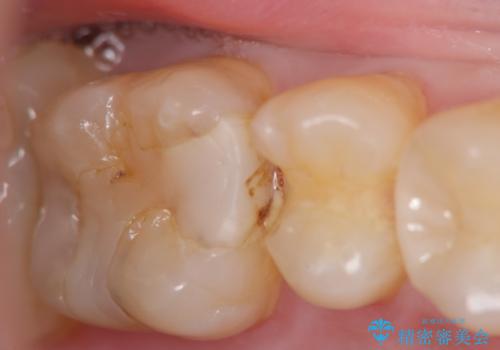

窩洞形態により選択するインレーの素材

- 定期検診を希望され来院、虫歯が発見されたため治療へと移行しました。

虫歯の大きさや残存歯質・窩洞形態によりゴールドやセラミックといった材質を選択することでより歯を削る量を少なくすると同時に強度も確保、長期的な予後を期待できるような治療を実践していきます。

セラミック・ゴールド共に化学的な変化が少なくインレー素材として理想的ですが、色調や強度・加工のしやすさ・最低限必要な厚み等の条件が異なります。

今回の治療では、虫歯を除去したのちより修復に適した素材を選択することで歯を削る量を可及的に少なくすることと、長期的な予後を期待できるような状態にすることができました。